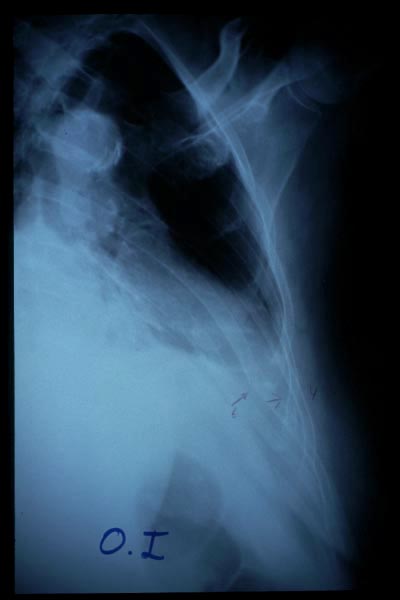

Fractura de húmero, intensa desviación de fragmentos

Fractura de húmero.

Fractura compleja de húmero.